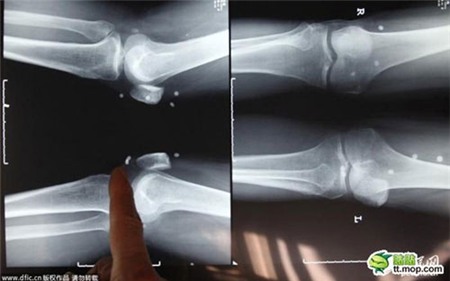

Hình ảnh những viên trân châu mắc kẹt trong các khớp xương đùi người đàn ông 61 tuổi.